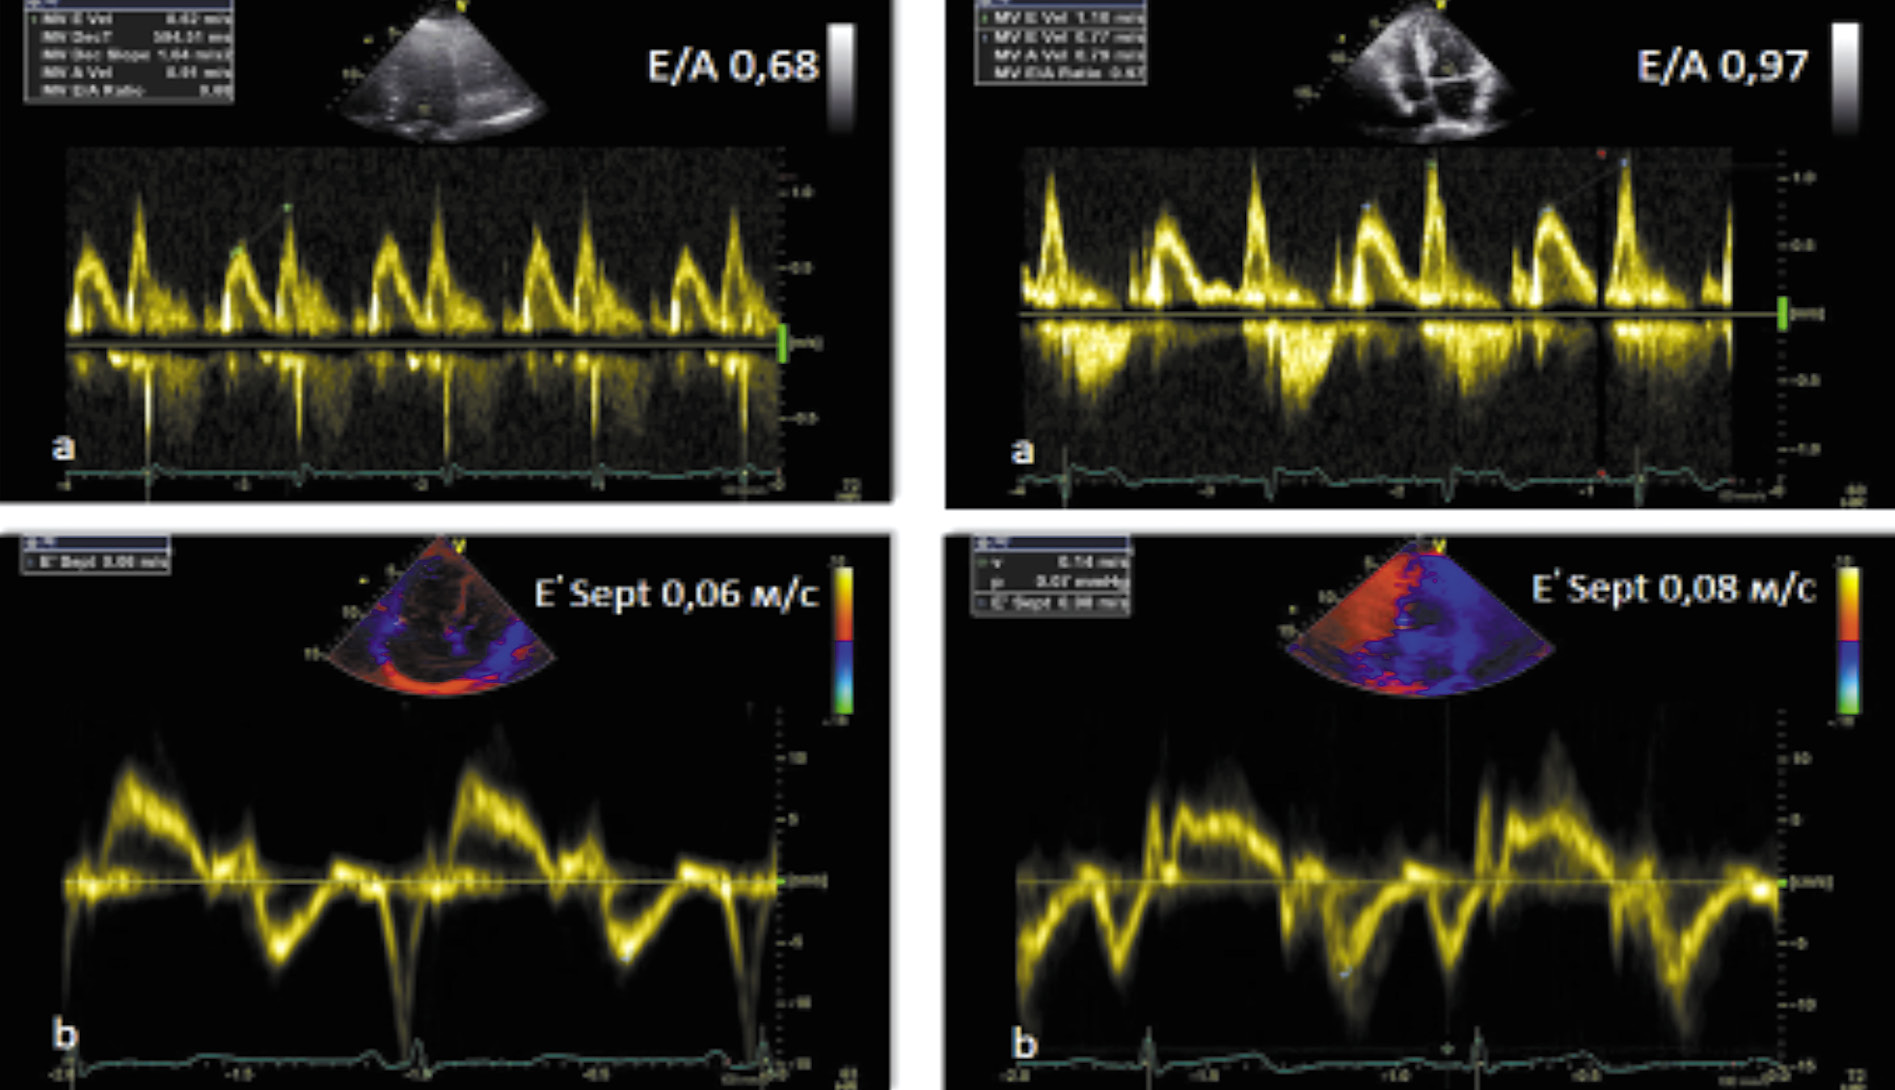

По результатам ЭхоКГ: при трансмитральной допплерографии отмечено увеличение максимальной скорости раннего диастолического наполнения ЛЖ (Е) по отношению к максимальной скорости наполнения ЛЖ в систолу предсердия (А), что говорит об улучшении релаксационных свойств миокарда. Кроме того, по данным тканевой миокардиальной допплерографии, являющейся наиболее чувствительным методом диагностики ранней ДД, отмечено улучшение показателей ДФЛЖ – увеличение скоростных показателей движения фиброзного кольца от латеральной (Еml) и септальной (Ems) стенок ЛЖ, что, в свою очередь, привело к снижению давления наполнения ЛЖ в виде уменьшения показателя Е/Еm (табл. 5, рис. 1).

Е/А | 0,68 | 0,97 |

Е/Еm | 11,2 | 10,4 |

Eml, м/с | 7 | 8 |

Ems, м/с | 6 | 8 |

Рис. 1. ДФЛЖ по данным трансмитрального потока (a) и тканевого миокардиального допплера (b) до и после лечения семаглутидом.